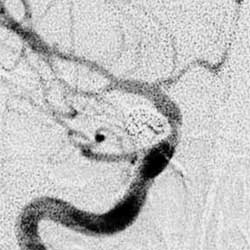

4.顱內血管造影有時可見頸動脈不規則狹窄有時也可見眶內塊狀影像。

動脈瘤疼痛性眼肌麻痹的診斷應與眼肌麻痹性偏頭痛、垂體瘤卒中、痛性糖尿病性眼肌麻痹以及頸內動脈瘤相鑑別。眼肌麻痹性偏頭痛與疼痛性眼肌麻痹有時難以區別有人認為此兩種疾病的表現為同一種疾病的不同階段。故而在診斷疼痛性眼肌麻痹時需非常慎重。

1.動脈瘤 顱底動脈環或頸內動脈的動脈瘤能引起動眼和(或)展神經麻痹,海綿竇內的頸內動脈瘤可引起動眼、滑車展與三叉神經眼支麻痹,稱為海綿竇綜合徵大腦後動脈、小腦上動脈、後交通動脈的動脈瘤都能導致動眼神經麻痹,但是一般不會單獨導致滑車神經麻痹。其腦神經麻痹的產生機制可能是囊狀動脈瘤急性擴張,壓迫或牽拉神經;靜脈淤血導致神經水腫;出血導致蛛網膜粘連等原因

2.顱內血管造影一般無特殊發現。